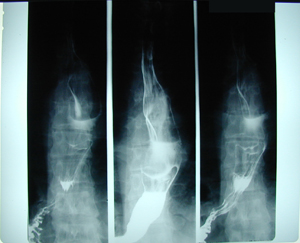

Εικόνα 1

Ακτινογραφία οισοφάγου μετά από την κατάποση βαριούχου γεύματος. Υπάρχει έλλειμμα πληρώσεως του αυλού του οισοφάγου, όπως και διάταση του αυλού.